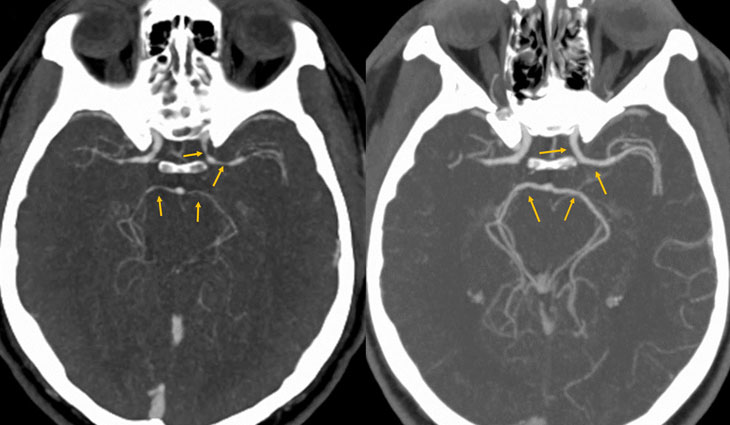

After eating a very spicy pepper, a diner’s brain arteries narrowed severely (arrows at left) and a pounding headache developed. Within five weeks, the arteries had returned to normal size (right).

Initial tests didn’t find anything strange. But when doctors scanned blood vessels in his brain, they found the man’s arteries had narrowed. Treatment included drinking a lot of water and taking pain medicine. Only then did the headaches stop. Five weeks later, the researchers looked at his brain once more. By this time, those brain arteries were back to normal size.